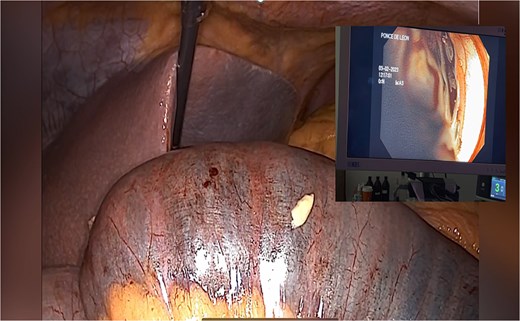

A dilated biliopancreatic loop was identified during surgery (Fig. 3). Endoscopy showed an intestinal obstruction from a blood clot at the anastomotic site (Fig. 4). The previous suture was removed (Fig. 5). With delicate traction the hemobezoar was extracted (Fig. 6). A new enterostomy was performed, and the lesion was sutured in two planes (Fig. 7). A liquid diet was initiated 24 hours after surgery, and the patient was discharged 72 hours later without complications.

Endoscopy shows hemobezoar at the site of gastrojejunal anastomosis.